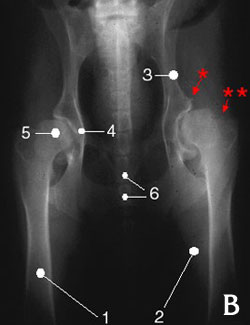

Hanches dysplasiques

Remarquer :

• la fonte (atrophie) musculaire (B2 vs A2).

• l'ostéoarthrose (dégénérescence des surfaces articulaires) qui se manifeste par une irrégularité de l'acétabulum (B4 vs A4) ainsi que par la présence d'ostéophytes (petites aspérités comme en *).

• le remodelage de la tête fémorale (**).